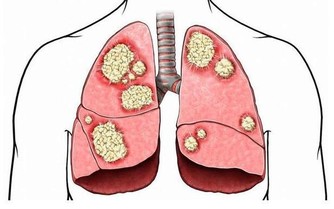

頸椎病患者更適合仰臥,這樣可以順應頸椎的生理彎曲,為達到枕頭支撐頸部的目的,患者最好將蕎麥皮枕頭的形狀稍加整理,使其形成一個中間凹、兩邊凸的形狀,高起的部分相當於自己的拳頭。睡眠時儘量枕著中間凹的部位,開始時不太習慣,經過長期適應,可以最大程度減少睡眠過程中的翻身動作。 蕎麥皮枕頭的適應性強,填充枕頭時,不要填得太滿,否則影響其塑形,填充約70%即可。(蘇玉梅)